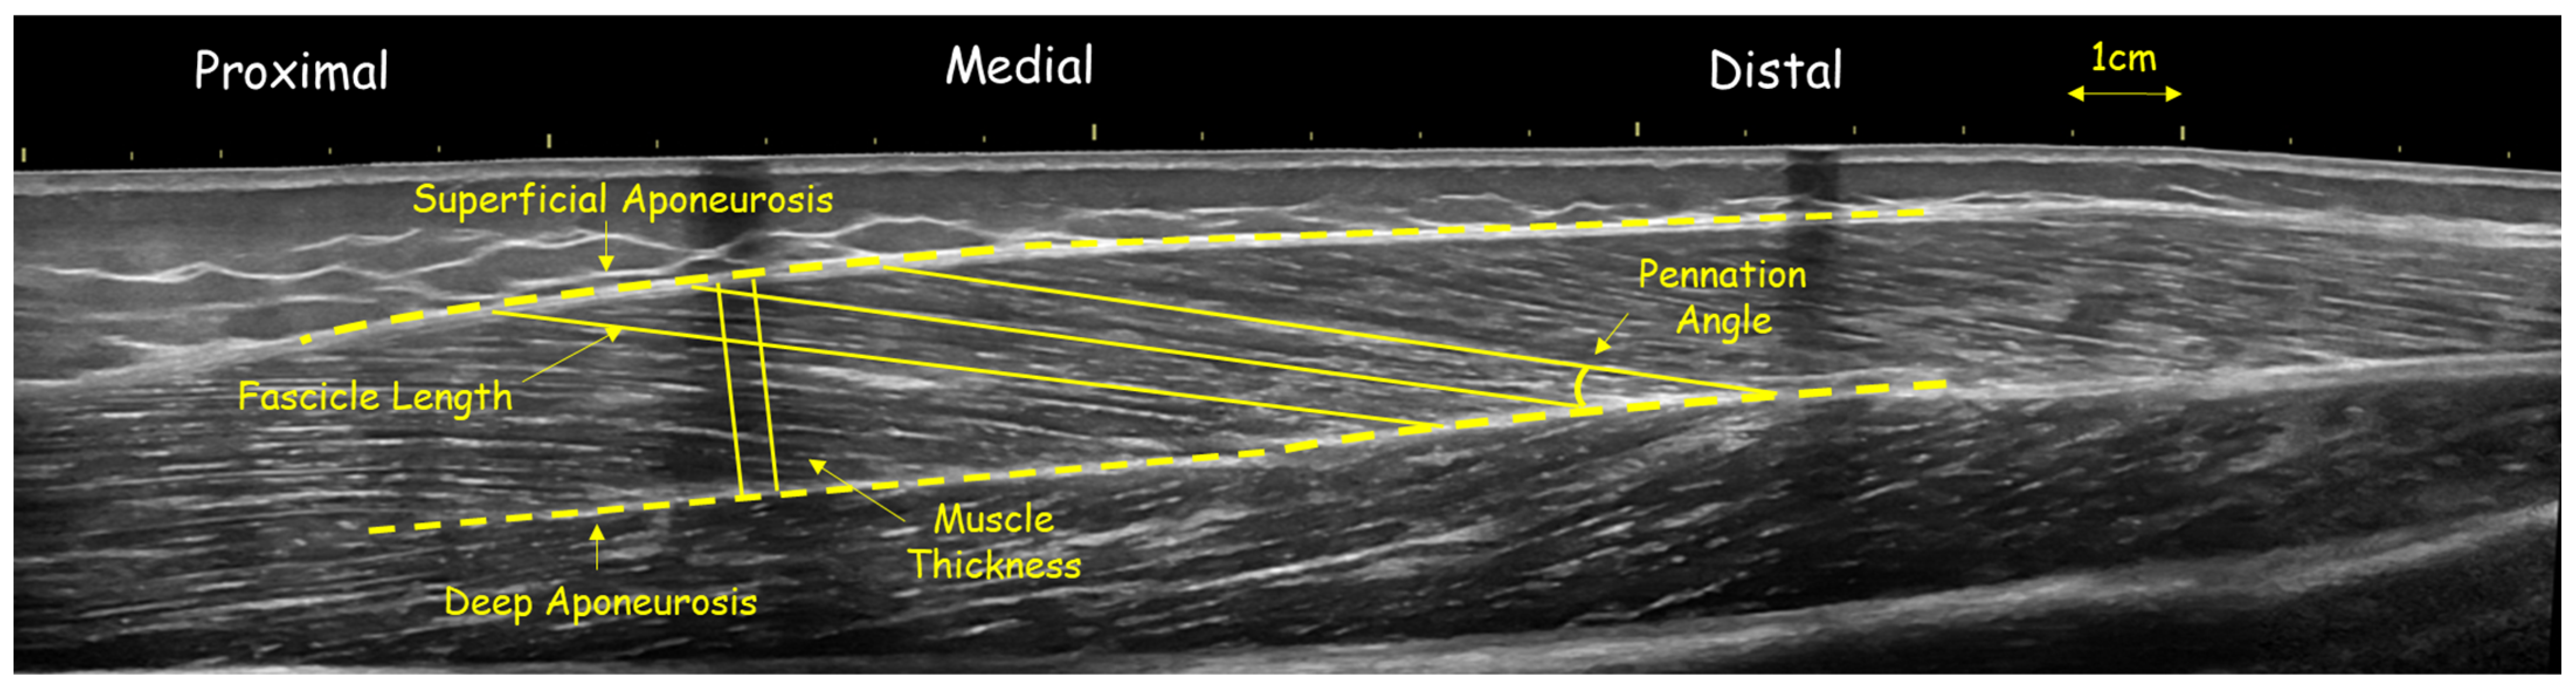

2.4. Ultrasonography